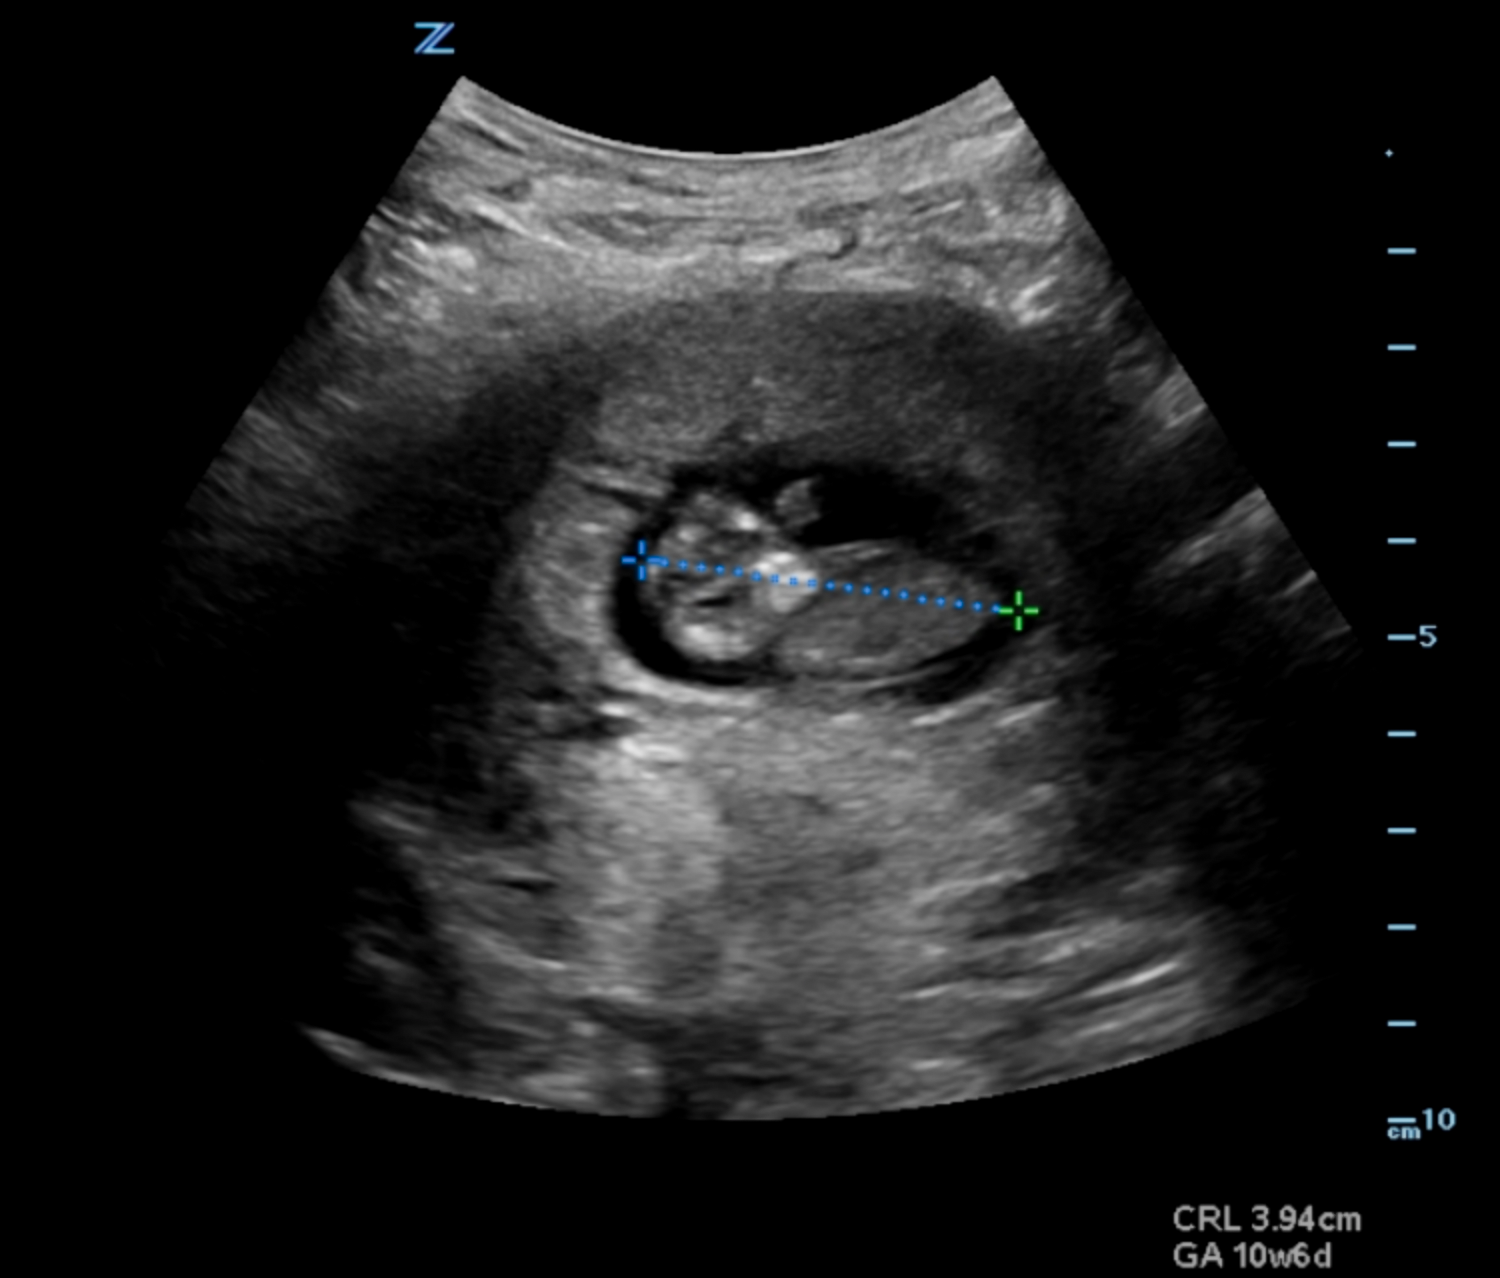

Crown Rump Length 10 Weeks . crown rump length (crl) on ultrasounds. calculates gestational age from crown rump length and expected nuchal translucency thickness. It is the most accurate estimation of gestational. in general, the crl measurement can range from 2 to 4 mm in the earliest stages of pregnancy, around 5 to 12 weeks. crown rump length (crl) is the length of the embryo or fetus from the top of its head to bottom of torso.

How To Measure Crown Rump Length (CRL) On Ultrasound Intrauterine Crown Rump Length 10 Weeks crown rump length (crl) on ultrasounds. in general, the crl measurement can range from 2 to 4 mm in the earliest stages of pregnancy, around 5 to 12 weeks. crown rump length (crl) is the length of the embryo or fetus from the top of its head to bottom of torso. calculates gestational age from crown. Crown Rump Length 10 Weeks.

10 weeks fetus ultrasound. CRL measured. Detailed view. Head, body Crown Rump Length 10 Weeks crown rump length (crl) is the length of the embryo or fetus from the top of its head to bottom of torso. calculates gestational age from crown rump length and expected nuchal translucency thickness. in general, the crl measurement can range from 2 to 4 mm in the earliest stages of pregnancy, around 5 to 12 weeks.. Crown Rump Length 10 Weeks.